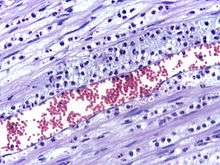

Leukocyte extravasation occurs mainly in post-capillary venules, where haemodynamic shear forces are minimised. This process can be understood in several steps, outlined below as "chemoattraction", "rolling adhesion", "tight adhesion" and "(endothelial) transmigration". It has been demonstrated that leukocyte recruitment is halted whenever any of these steps is suppressed.

The cytoskeletons of the leukocytes are reorganised in such a way that the leukocytes are spread out over the endothelial cells. In this form, leukocytes extend pseudopodia and pass through gaps between endothelial cells. Transmigration of the leukocyte occurs as PECAM proteins, found on the leukocyte and endothelial cell surfaces, interact and effectively pull the cell through the endothelium. Once through the endothelium, the leukocyte must penetrate the basement membrane. The mechanism for penetration is disputed, but may involve proteolytic digestion of the membrane, mechanical force, or both.[3] The entire process of blood vessel escape is known as diapedesis. Once in the interstitial fluid, leukocytes migrate along a chemotactic gradient towards the site of injury or infection.